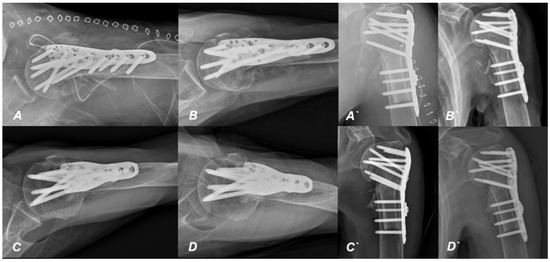

2. Case Presentation

Surgical Technique